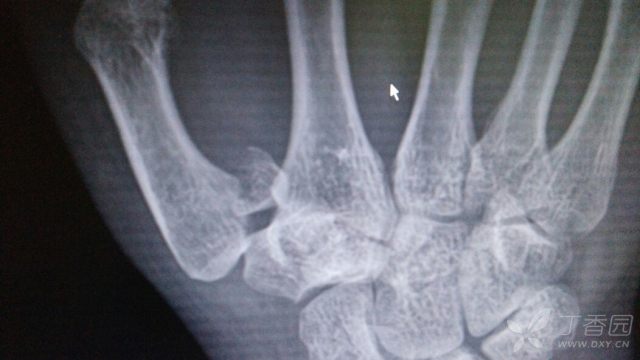

第一掌骨基地部骨折!

640x360 - 28KB - JPEG